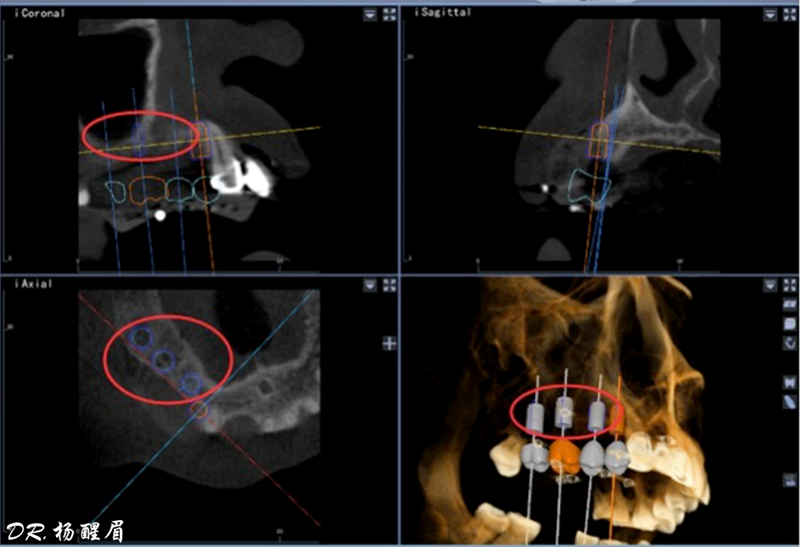

處理:通過數(shù)字化種植導航進行15、16、17種植修復

®使用迪凱爾易植美導航軟件進行方案設計,確定種植體使用方案,以及種植位點,方向和深度

®多顆植體種植方案應盡量保持軸向在同水平線上

®按照術前方案進行備洞及植體植入,醫(yī)生可以通過屏幕軟件引導對手術中植入點、角度、深度實時追蹤

®對植體深度及方向進行確認

®完成3顆植體的植入,植體位點如術前方案設計,均在同軸線。